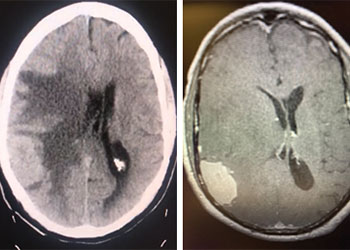

Brain:

Cerebellar Hemangioblastoma

Author: Michael Brisman M.D., F.A.C.S., Read More!